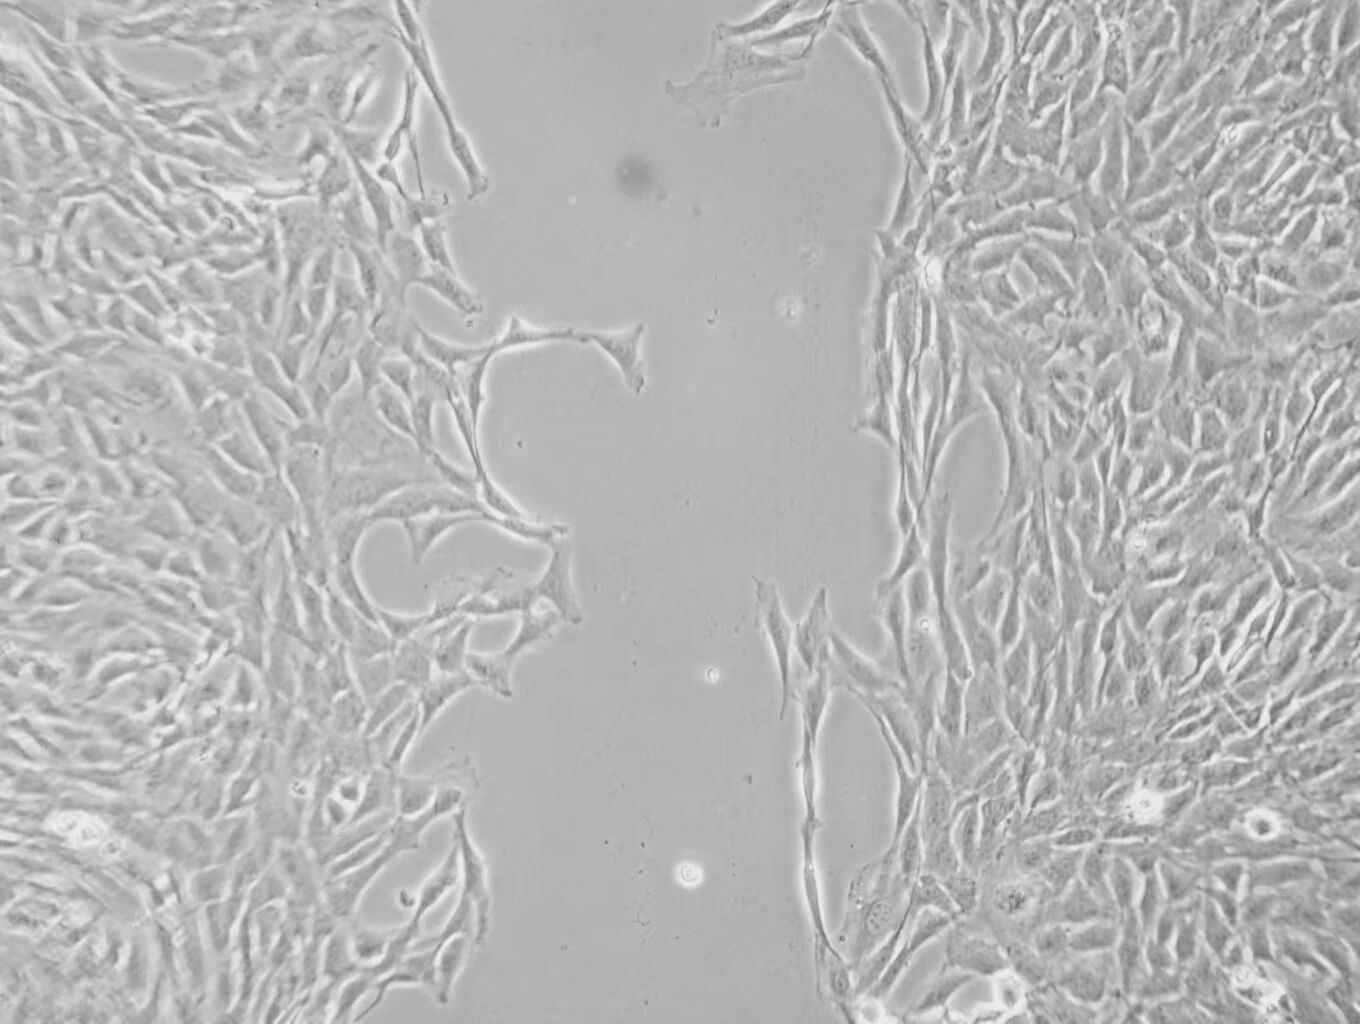

研究中采用Boyden小室实验与伤口愈合实验(划痕实验)对VSMCs的迁移能力进行了定量评估。实验的成功离不开明美的倒置荧光显微镜MF53-N,协助团队验分别在0小时和24小时拍摄创面愈合情况,并计算细胞的迁移距离。其高清成像与超长工作距离的特点帮助研究人员简单清晰地观察到血管平滑肌细胞在不同时间点的迁移变化,为高血压血管重构的研究提供了强有力的数据支持。